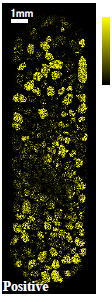

カプセル剤タイプ薬の断面についてTOF-SIMSによる質量イメージング分析を行いました。断面加工を行い、薬剤全体(約7mm×20mm)とその内部の顆粒一粒(約500μmΦ)に着目したイメージング事例をご紹介します。

光学顕微鏡像とTOF-SIMSイメージング

| 光学顕微鏡 | ●成分A | ■成分B | ▼成分C | |

●成分A:イブプロフェン

■成分B:デキストロメトルファン臭化水素酸塩水和物

▼成分C:無水カフェイン